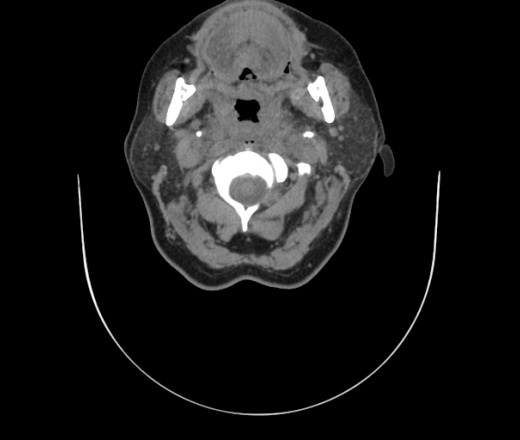

Женщина поступила в х/о спустя 4 дня после того как при употреблении карася подавилась костью.

Наличие газа в средостении на протяжении тел С2-С6 (медиастинальна эмфизема); рыбная кость на уровне тела С6.

При всем уважении, но говорить о медиастинальной эмфиземе, оценивая мягкие ткани шеи, как-то слишком резко. На мой взгляд, это ретрофарингеальное пространство.

Эвакуировали почти 100мл гноя. Но кость не смогли найти. Думаю что она даст дальнейшее ослоднение. Эндоскопически за черпалонадгортаной звязкой не смогли зайти в пищевод, все мягкие ткани отечные, просвет пищевода сдавлен. По всей видимости параэзофагеальная клетчака тоже задействована. Эмпиема, если ее можно так назвать, незнаю как правильно дошла до уровня яремной вырезки. Чем закончиться напишу. Ждем медиастинита.

Флегмона заглоточного пространства шеи, только операция, флегмоны вскрывают. Риск медиастинита.

Согласен с Вами; конечно, наличие газа в клетчатке ретрофарингеального пространства (затмение с опечаткой..). К сожалению, процесс "продвигается" к медиастиниту. Но почему никто, не отмечает наличие рыб. кости; или это для Всех очевидно?

Так вы уже отметили. Хотя ориентировал бы не скелетотопически, а на перстнечерпаловидный сустав.

Кость то мы сразу выявили, размеры где то 17*2мм, но ее так и не получается найти в этой каше